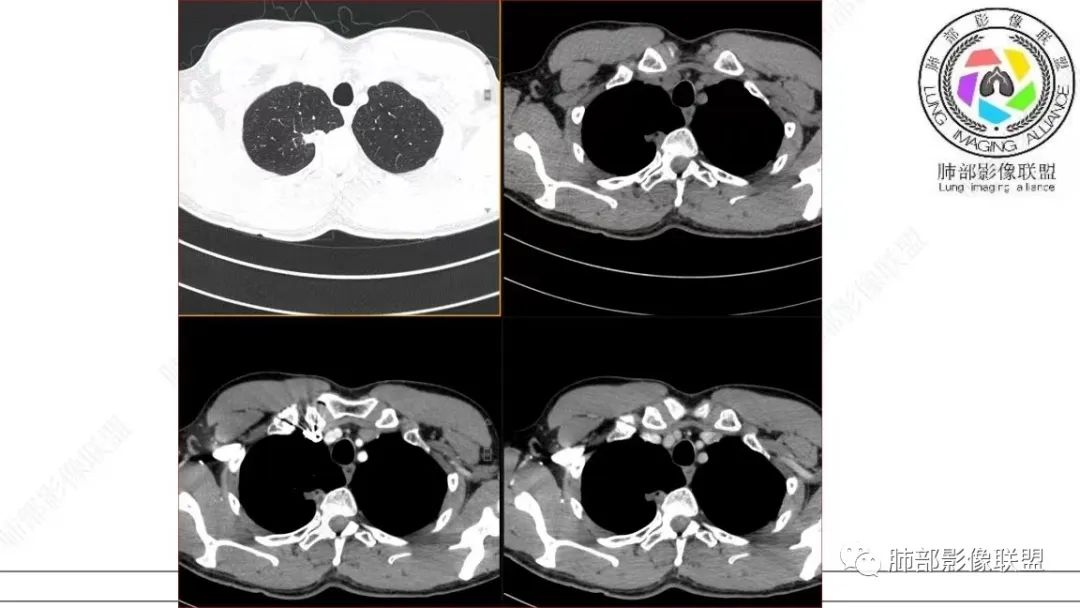

飞鹰行动:中年男性,右肺上叶不规则病灶,与胸膜粘连,多发长毛刺,周围模糊的磨玻璃影,相邻胸膜增厚,增强病灶中度以上强化,内见血管影,没有重建图像,感觉病灶符合良性病变征象多一些,考虑炎性病变,OP?

小兜:男,50岁,体检发现右肺上叶胸膜下不规则软组织结节,分叶,长毛刺,与胸膜相连,胸膜增厚,渐进性强化,强化不均匀,内部可见小灶状低强化灶,内部血管穿行。首先考虑肉芽肿性病变,鉴别腺癌

影像诊断

本研究对22处BA的CT影像进行分析,发现以下方面对诊断本病有一定提示意义:①病变部位:本组病例均为周围型病变,多位于下叶,且以胸膜下区为主,与既往研究结果一致。本病细支气管黏膜上皮的起源赋予了其特有的位置分布。②类型:本组GGO14处,实性结节8处。Chang等收集的14处BA中,GGO6处、实性结节8处,与既往研究结果基本一致。此外,部分学者报道呈空洞表现的BA。由此可见,BA的影像表现多样,但主要表现为GGO和实性结节。③大小:本研究显示BA普遍较小,最大径约(0.9±0.7)cm,95%的病变不超过2.0cm。王蓓等、高何等分别纳入8例、15例BA,病灶平均最大径均为1.0cm,与本研究结果一致。④形态:本组BA无论表现为GGO还是实性结节,其形态不规则且边缘毛糙,仅少部分体积较小的BA可呈类圆形或椭圆形,与Kamata等的研究结果相似,推测BA的形态学改变与肿瘤无包膜有关。⑤伴发征象:本研究中BA多伴有中央或外周空泡征、细支气管充气征及血管征,其中以中央空泡征最具特征。刘芳兵等报道2例表现为GGO的BA均伴空泡征;苏雷等报道11例BA中,伴有空泡征8例、血管征10例。可见空泡征和血管征对诊断本病具有重要意义。上述征象与镜下瘤内、瘤周常见细支气管及伴行的厚壁血管有关。此外,胸膜牵拉征、分叶征及毛刺征罕见。⑥强化方式:实性结节表现的BA增强扫描呈延迟性显著强化,部分病灶动脉期可见血管造影征,血管走行自然,未见破坏。血管造影征与镜下病变常见细支气管动脉束穿行相符,此征象也反映了肿瘤位于细支气管周围的定位。⑦随访中病灶保持稳定或缓慢增长。此段内容及病例图片摘自并感谢,黄勇教授、王越老师-细支气管腺瘤的CT表现,发表于中国医学影像杂志。